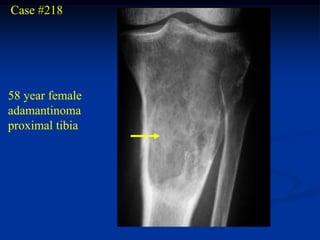

Case #218

58 year female

adamantinoma

proximal tibia

Lateral view